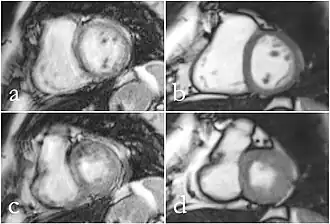

Although applications of real-time MRI cover a broad spectrum ranging from non-medical studies of turbulent flow[27] to the noninvasive monitoring of interventional (surgical) procedures, the most important application making use of the new capabilities is cardiovascular imaging.[1] Previous cardiac MR (CMR) used cine techniques to capture the periodic motion of the heart. However, this is not feasible for patients with arrhythmia, where the cardiac cycle is unpredictable.[28] With the new method it is possible to obtain movies of the beating heart in real time with up to 50 frames per second during free breathing and without the need for a synchronization to the electrocardiogram.[29] A study performed by Laubrock et al.[28] demonstrated that RT-MRI produced higher quality images with a higher SNR than cine CMR with a bSSFP sequence and radial k-space sampling. RT-MRI also removes the need for breath-holding while imaging, leading to a more comfortable experience for the patient as well.[28]